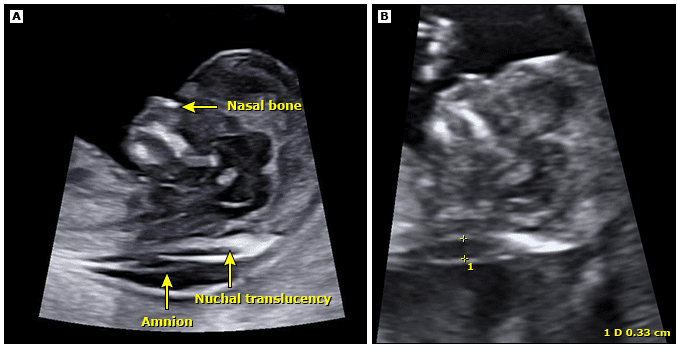

Translucência nucal

A translucência nucal corresponde ao espaço livre na parte posterior do pescoço fetal, entre a coluna e a borda da pele, sendo medida no plano sagital médio fetal e podendo representar maior risco de alterações genéticas fetais quando aumentada.

Osso nasal ausente

Normalmente, o osso nasal é visto através do plano sagital mediano como uma linha mais ecogênica do que a pele subjacente. A ausência do osso nasal em ultrassonografia do primeiro trimestre pode indicar aneuploidias, como trissomia 13, trissomia 18 e trissomia 21.

Realiza-se a triagem com ultrassom morfológico entre 11 semanas e 0 dias e 13 semanas e 6 dias. Entre os achados do exame que associam-se a aneuploidias estão:

- Translucência nucal (TN) maior ou igual a 3 ou 3,5 mm;

- Osso nasal ausente;